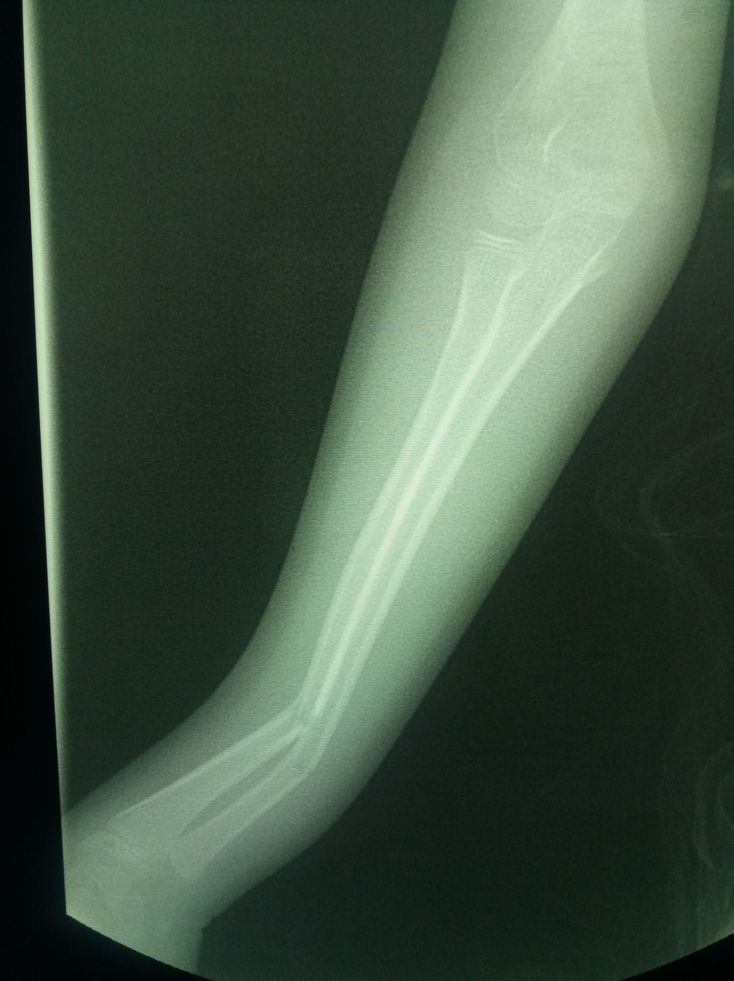

Green stick fracture

The patient is kid but it is not green stick fx. Its double fx of fore arm

Double fracture of forearm.

Linear fracture of shaft of radius &ulna